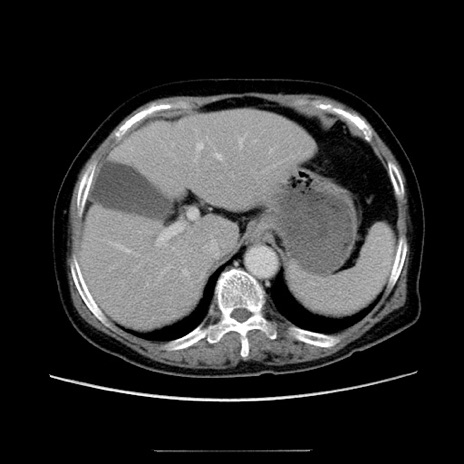

症例5(横断像)

【症例】70歳代女性

【主訴】お腹が張る

【現病歴】1週間くらい前から腹部膨満の自覚あり。昨日夜から増悪したため、本日救急外来受診。

【身体所見】意識清明、BT 36.5℃、BP 165/106mmHg、HR 80bpm、SpO2 98%、腹部:膨満、軟、自発痛・圧痛なし、触診にて不快感あり、腸蠕動音:減弱

【データ】WBC 12600、CRP 1.04